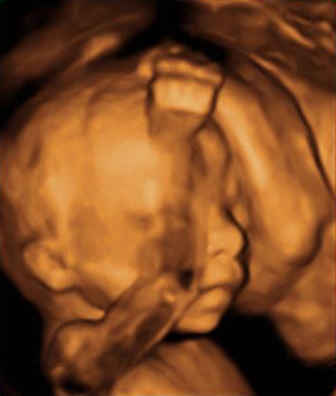

Ecografía 4D: Cómo es un bebé con el dedo en la boca

Esta ecografía 4D de la semana 20 de embarazo muestra que los bebés prácticamente empiezan a chuparse el dedo dentro del útero materno. El feto se acerca el dedo pulgar a la boca y en las imágenes finales la abre, muy probablemente para chupárselo.

Perfil de un bebé con el dedo pulgar cerca de la boca

En las imágenes del final, se puede apreciar cómo la criatura incluso abre la boca, quizá para chuparse el dedo pulgar. Es un reflejo el de succión que mantendrá fuera del útero, ya sea con su propio dedo o mediante la lactancia materna.